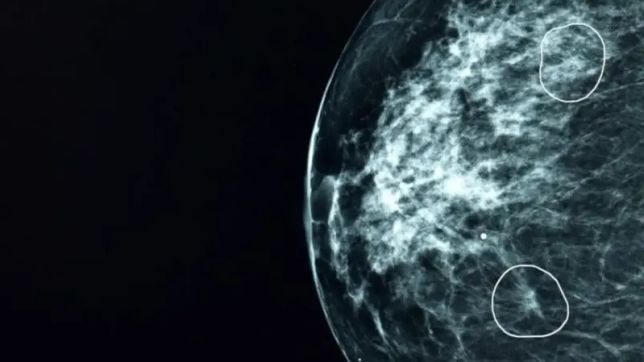

Duas áreas de preocupação destacadas por ferramenta de IA

A ferramenta, chamada Mia, foi testada em conjunto com médicos do NHS e analisou mamografias de mais de 10 mil mulheres. Na maioria dos exames, Mia não identificou indícios de câncer, mas sinalizou com sucesso todos aqueles em que havia indícios apontados por médicos antes, além de outros 11 em que os médicos não haviam identificado tumores.

Nos estágios iniciais, o câncer pode ser extremamente pequeno e difícil de detectar.Bárbara foi um dos 11 pacientes cujo câncer foi identificado por Mia e que não havia sido detectado em exames por médicos do hospital. Como seu tumor de 6 mm foi detectado muito precocemente, ela foi operada e precisou apenas de cinco dias de radioterapia. Pacientes com câncer de mama com tumores menores do que 15 mm quando descobertos têm uma taxa de sobrevivência de 90% nos cinco anos seguintes.